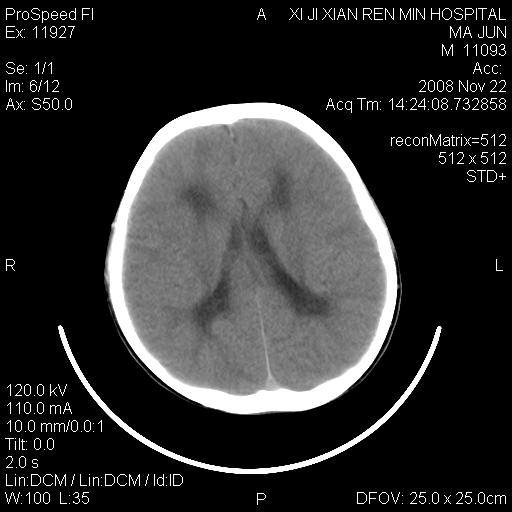

双侧侧脑室前角,三角区旁及半卵圆中心区白质呈低密度改变,半卵圆中心区病灶呈片状融合趋势,无软化征像,脑室无扩张,各神经核团无异常改变,脑皮质无萎缩等征像,结合病史考虑髓鞘发育不良性脑白质病,异染性脑白质营养不良可能性大.不除外多发性硬化等其他改变,建议磁共振检查

脑白质减少,双侧侧脑室额角旁及半卵圆中心可见对称性略低密度影,边缘尚清,考虑脑白质发育不良